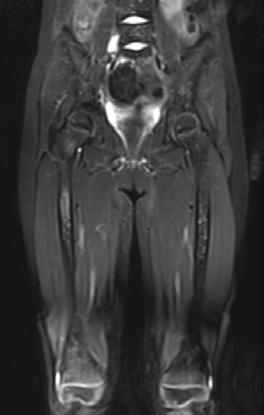

Femenino de 7 años con diagnóstico de Neuroblastoma, se realiza PET/RM con [18F]F-DOPA para estadiaje, con evidencia de lesión primaria a nivel de retroperitoneo y conglomerados locoregionales así como infiltración a médula ósea del esqueleto axial y apendicular (Figura 1A), posteriormente la paciente fue tratada quirúrgicamente con resección de la lesión primaria así como tratamiento con inmunoterapia y transplante autólogo de médula ósea además de radioterapia. Al presentar refractariedad al tratamiento comentado, se plantea la posibilidad de administrar Lutecio (177Lu) oxodotreotide, por lo que se sugiere realizar PET/RM con [18F]Octreotide para valorar expresión de receptores de somatostatina y considerar la terapia con radionúclidos para receptores de péptidos (PRRT), el estudio muestra evidencia de sobreexpresión anormal de dichos receptores en retroperitoneo, espacio subpleural izquierdo además de esqueleto axial y apendicular (Figura 1B).

Estudio PET con 6-[18F]DOPA 3A) y [18F]OCTREOTIDE 3B) en cortes coronales de secuencias T2 de miembros pélvicos y con imágenes fusionadas, donde se identifica mayor sobreexpresión anormal de los receptores de somatostatina al compararlos con 6-[18F]DOPA, y que hace candidata a la paciente para PRRT.